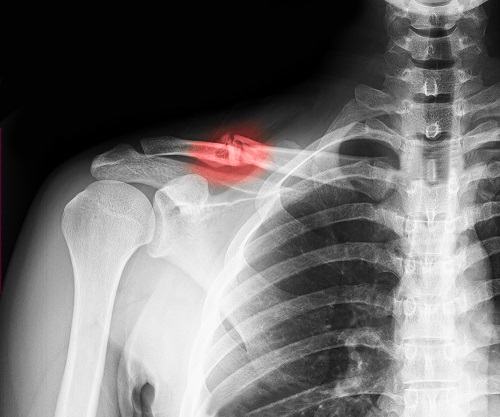

Xương đòn là phần xương quai xanh, dễ nhìn thấy nhất khi chúng ta mặc áo hở là phần xương nâng đỡ trọng lượng cả cánh tay. Gãy xương đòn xảy ra khi có va chạm, tổn thương chấn thương ở vùng vai.

Xương đòn bị gãy sẽ ảnh hưởng đến hoạt động của cả cánh tay khiến tay yếu và cần hạn chết vận động.

Khi bị gãy xương đòn, người bệnh nên đến thăm khám và điều trị tại các cơ sở uy tín để đánh giá mức độ nghiêm trọng để có cách chữa trị phù hợp.